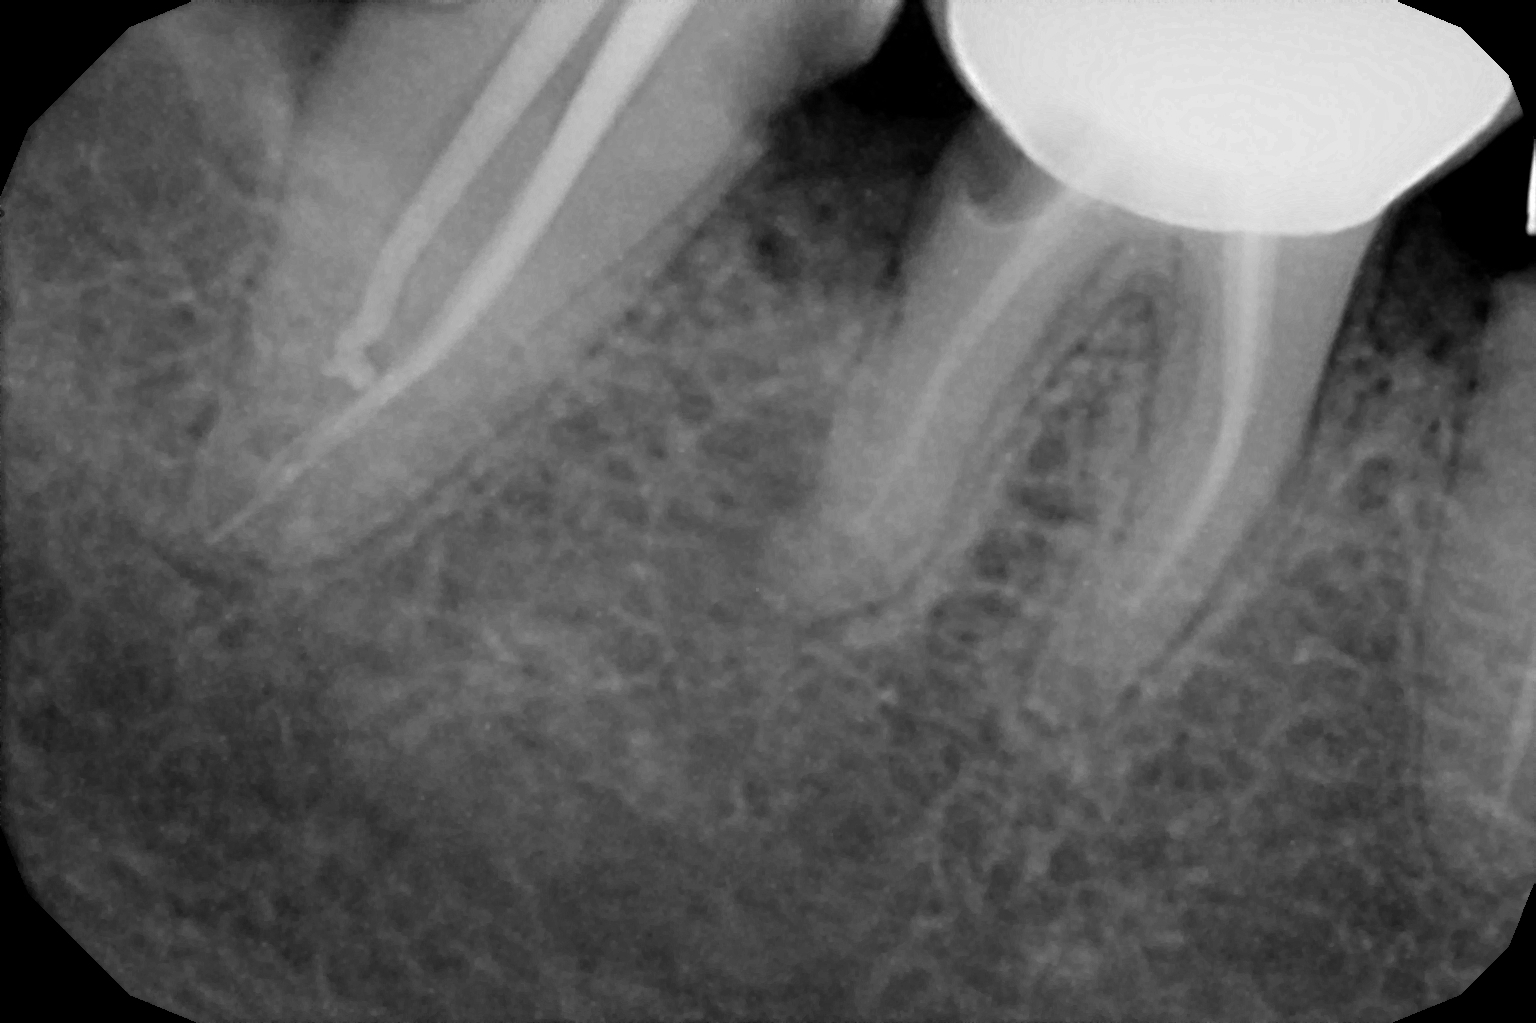

When the tooth is is sensitive to particularly hot and cold. When you cannot chew from that side or there is associated action of pain and swelling with same tooth, root canal treatment can save the tooth. For root canal treatment our clinic is equipped with state-of-the-art facility. We are following the protocol that is universally accepted and considered as a gold standard We are using rubber Dam for maximum possible cases. The root canal treatment is done under local anaesthesia that's why mostly it is painless . The rubber Dam isolation helps in proper irrigation and it provides much needed ease to the operating dental surgeon and the patient . The sealer and filling material are one of the Prime requisite of quality root canal treatment, it needs use of multiple X rays to really judge whether the results are acceptable or not. In older days root canal was just about cleaning the decade portion, removing the Pulp and filling it with biocompatible material but nowadays the root canal treatment it is very much advanced the precision is increased manifold. The materials and armamentarium that is required for efficient root canal have advanced in exclusion initial ways the the Abstract of all these things is the patients are getting great results after root canal treatment. Only the root canal is not sufficient to make a tooth functional again ,it needs use of Core buildup material and complete coverage Crowns according to the tooth position. During Covid19 time we have studied and implemented use of of high strength composites in our practice and the results of it are amazing many times it has saved tooth from being restored with crown. In some cases where the tooth is grossly carious we need a complete coverage crown. The materials and the Crown materials are are available in various price ranges. We prefer only the best of materials for our patients. We believe that to perform best treatment we need best of the armamentarium and best of the material for our patients who value and deserve the best of the treatment.